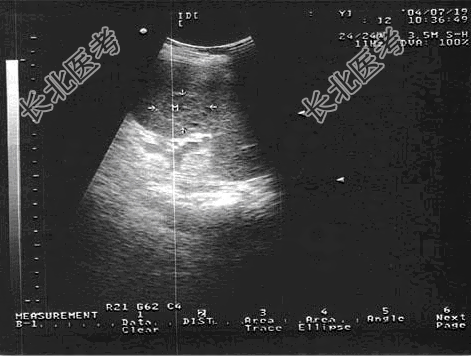

- 单项选择题女,19岁, 有淋巴瘤病史。结合超声检查如图,诊断为

A、脾淋巴瘤

B、脾血管瘤

C、脾结核

D、脾错构瘤

E、脾脓肿